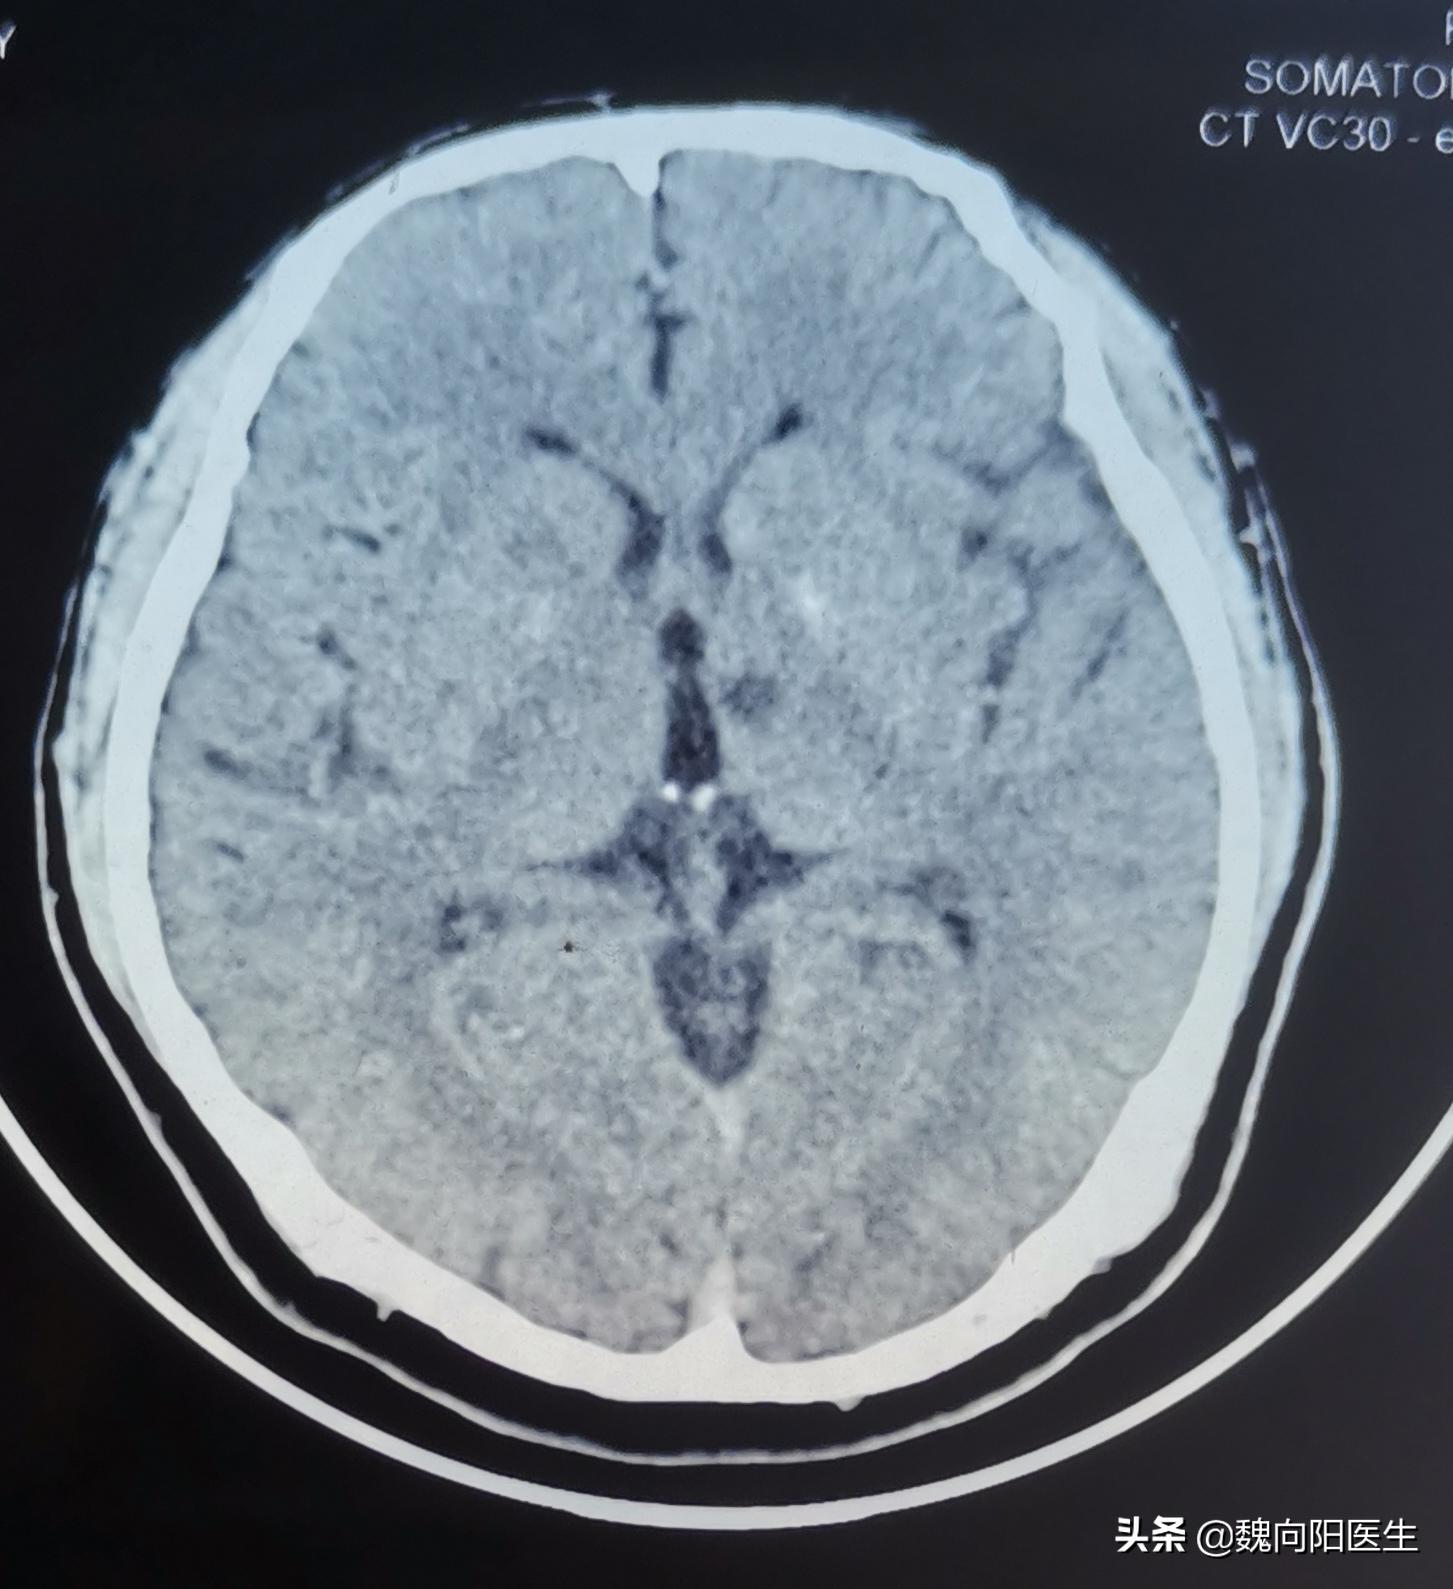

腔隙性脑梗死:是脑穿支小动脉闭塞引起的深部脑组织较小面积的缺血性坏死,主要病因是高血压和脑动脉硬化,好发部位为基底核区和丘脑区,也可发生于脑干、小脑等区域,可多发。

由于这些穿支小动脉的供血区域通常没有侧支循环,所以很容易发生缺血性梗死,形成直径0.2~15mm的囊性病灶,坏死组织被吸收后,残留下来小囊腔,即称为“腔隙性脑梗死”。